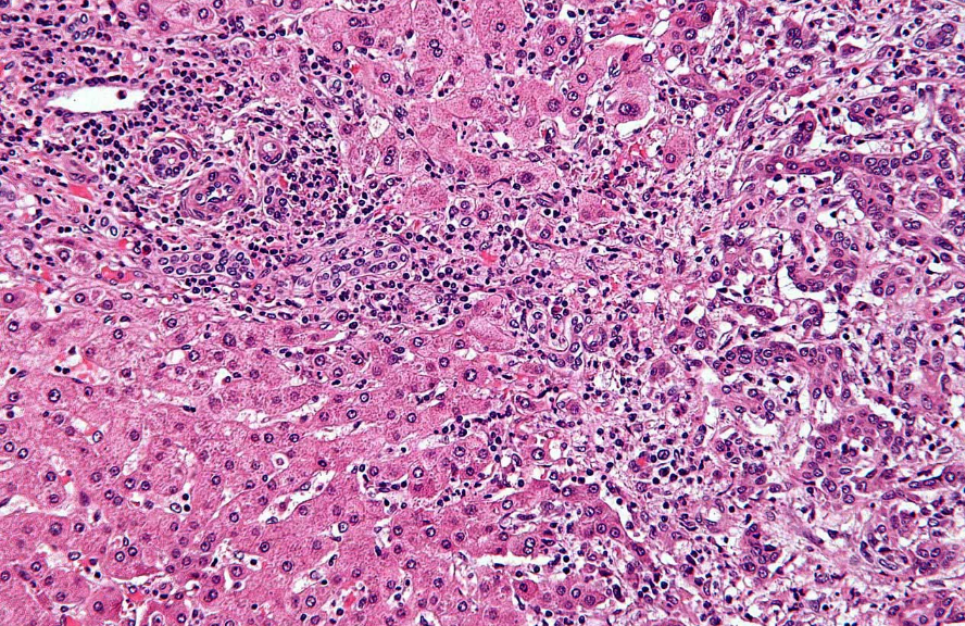

Внутрішньопечінкова холангіокарцинома. Гістологія. Зображення з відкритих джерелПацієнт може місяцями не знати про хворобу, поки рак не перейде в запущену стадію. Симптоми схожі на десятки інших захворювань, специфічних скринінгових тестів не існує, а п'ятирічна виживаність коливається від 7 до 20 відсотків залежно від стадії. Це холангіокарцинома — один із найсмертоносніших видів онкозахворювань, про який більшість людей ніколи не чули.